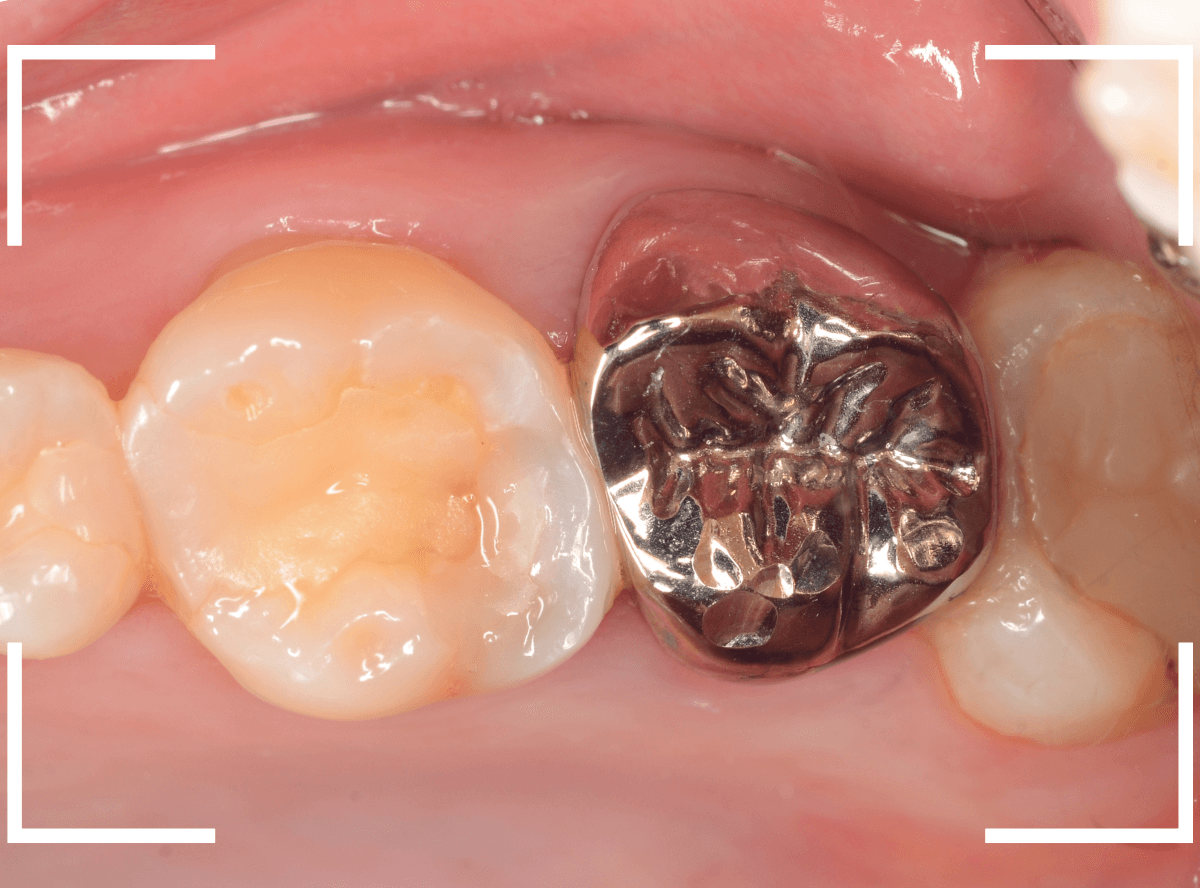

Case.20 メタル・インレーとメタル・クラウンをジルコニアにやり替え

「下の奥歯の銀歯を白くしたい」というご希望の患者さんです。

メタル・インレーとメタル・クラウンが入っていますね。

検査の結果、再製に問題なさそうでしたので、治療を進める事になりました。

まずは、奥のメタル・クラウンを外します。

メタル・コアが入っていますが、こちらも慎重に外して、中を調べていきます。

レントゲン写真では問題なさそうでしたが、メタルコアを除去すると、中は真っ黒でした。

このように、コアの中で虫歯が進行している場合もありますので、さし歯をやり直す際は、出来る限りコアも外して調べるようにしています。